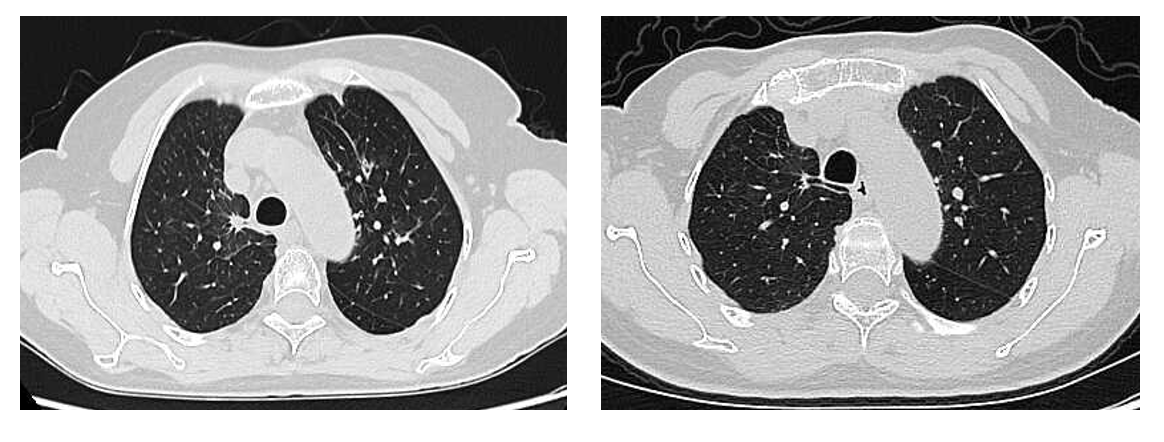

疗效评价:治疗仅1月余,2024年5月7日第一次疗效评估即达到部分缓解(PR),病灶较治疗前显著缩小(图1),治疗应答迅速且强效2024年7月31日第三次疗效评估仍维持PR状态,病灶在首次缩小的基础上持续退缩(图2),肿瘤负荷进一步降低。2026年1月13日最近一次肿瘤评估提示病灶接近CR(图2)。截止随访,患者已接受芦康沙妥珠单抗治疗22个月,PFS达22个月,疾病控制持续稳定,未出现进展迹象,实现了长期高质量生存。

图2. 2024年7月31日(左)对比2026年1月13日(右)